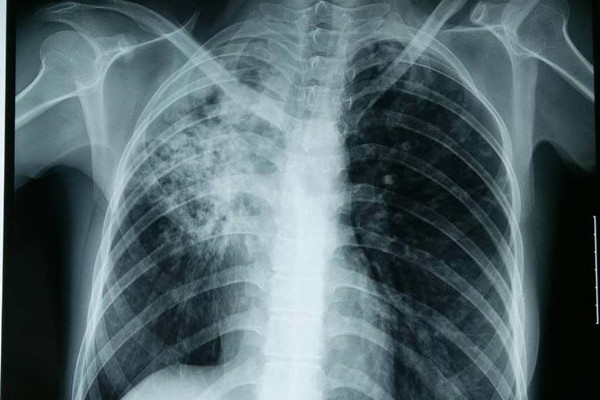

( 4) 胸部影像学提示有结核病灶;